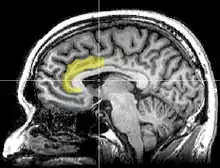

تحقق فان فين (Van Veen ) وزملاؤه من الأساس العصبي للتنافر المعرفي في نسخة معدلة من نموذج الامتثال المستحث الكلاسيكي باستخدام التصوير بالرنين المغناطيسي الوظيفي (fMRI)،وقد تسبب الاستجابة في تنشيط القشرة الحزامية الأمامية والفص الجزيري الأمامي. علاوة على ذلك، فإن مدى تنشيط هذه المناطق توقع درجة التغيير في مواقف الأفراد المشاركين. وقال فان فين وزملاؤه أن هذه النتائج تدعم نظرية التنافر الأصلية لفستنغر، وتدعم "نظرية الصراع" لعمل الحزامية الأمامية.